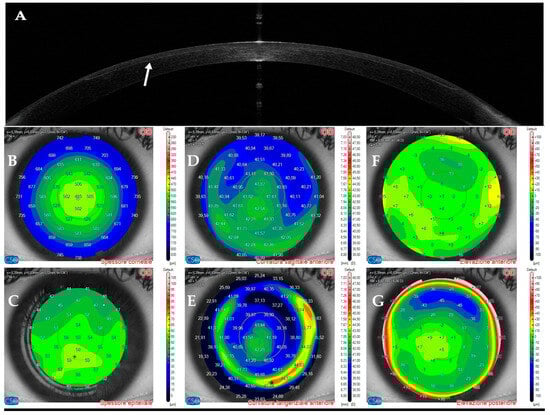

3.3. Patient #3